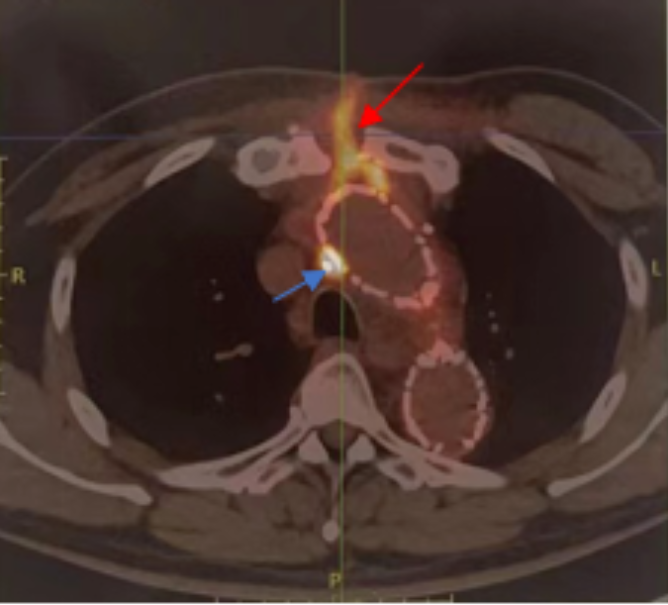

▲老周的PET/CT结果。红色箭头表示感染的窦道从人工血管/支架穿过胸骨直达皮肤表面,蓝色箭头标识人工血管周围脓肿

今年7月初,老周和家人抱着一线希望,辗转来到北京协和医院。苗齐教授接诊后,仔细为其分析了病情——人工血管及主动脉支架的感染不仅会引起发热、消耗,血管内感染赘生物的脱落还会导致脑梗、重要脏器的栓塞,而像老周这样存在人工血管周围脓肿、经窦道与外界相通的,还可能随时出现血管破裂、出血,甚至死亡。